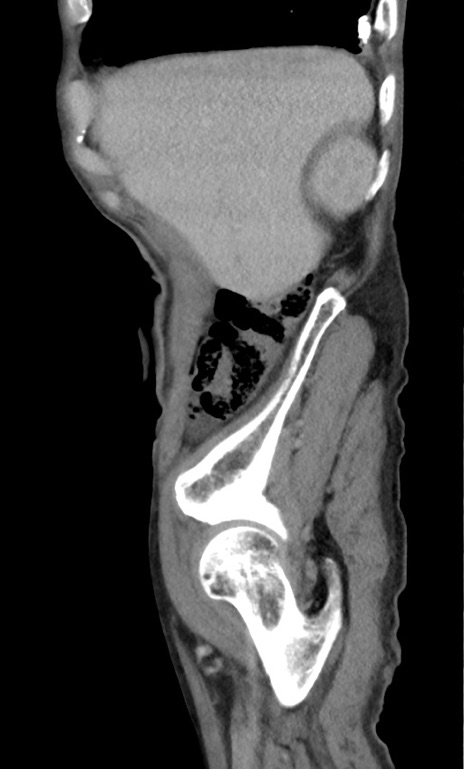

症例3(矢状断像)

症例

【症例】 70歳代男性

【主訴】右鼠径部腫瘤、疼痛

【現病歴】本日朝より上記主訴あり、受診。

【既往歴】膀胱癌にて膀胱全摘、両側尿管皮膚瘻

【データ】WBC 5600、CRP 0.56